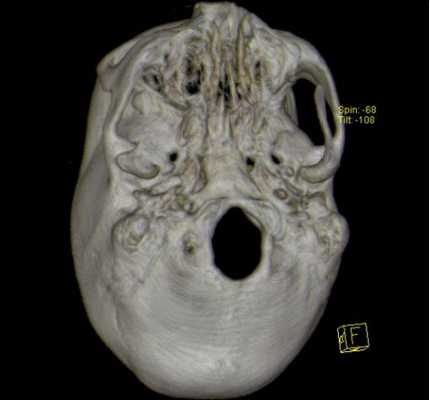

![3D-реконструкция с помощью компьютерной томографии]()

Основание черепа: вид изнутри и снизу

Из-за данных анатомических особенностей любая патология, возникающая в этой области, как правило, приводит к тяжелым последствиям. В подобных условиях для диагностики с успехом используется компьютерная томография основания черепа. Более того, КТ основания черепа может быть более информативным и специфичным методом обследования, по сравнению с магнитно-резонансной томографией.